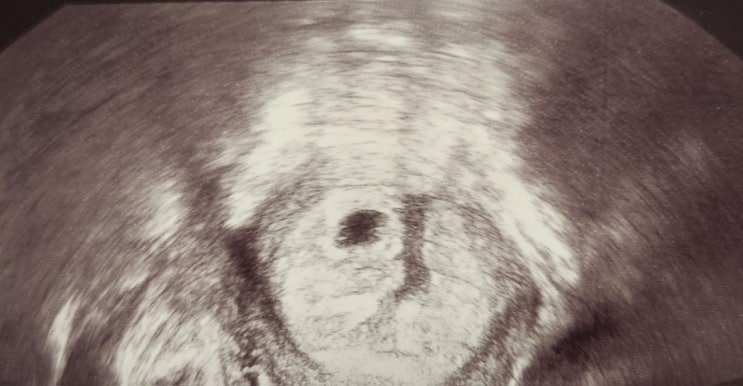

둘째를 임신한지 6주 3일차가 되었어요. 원래는 예상 7주 2일이 되는 날에 첫 초음파를 보려고 했어요. 그...